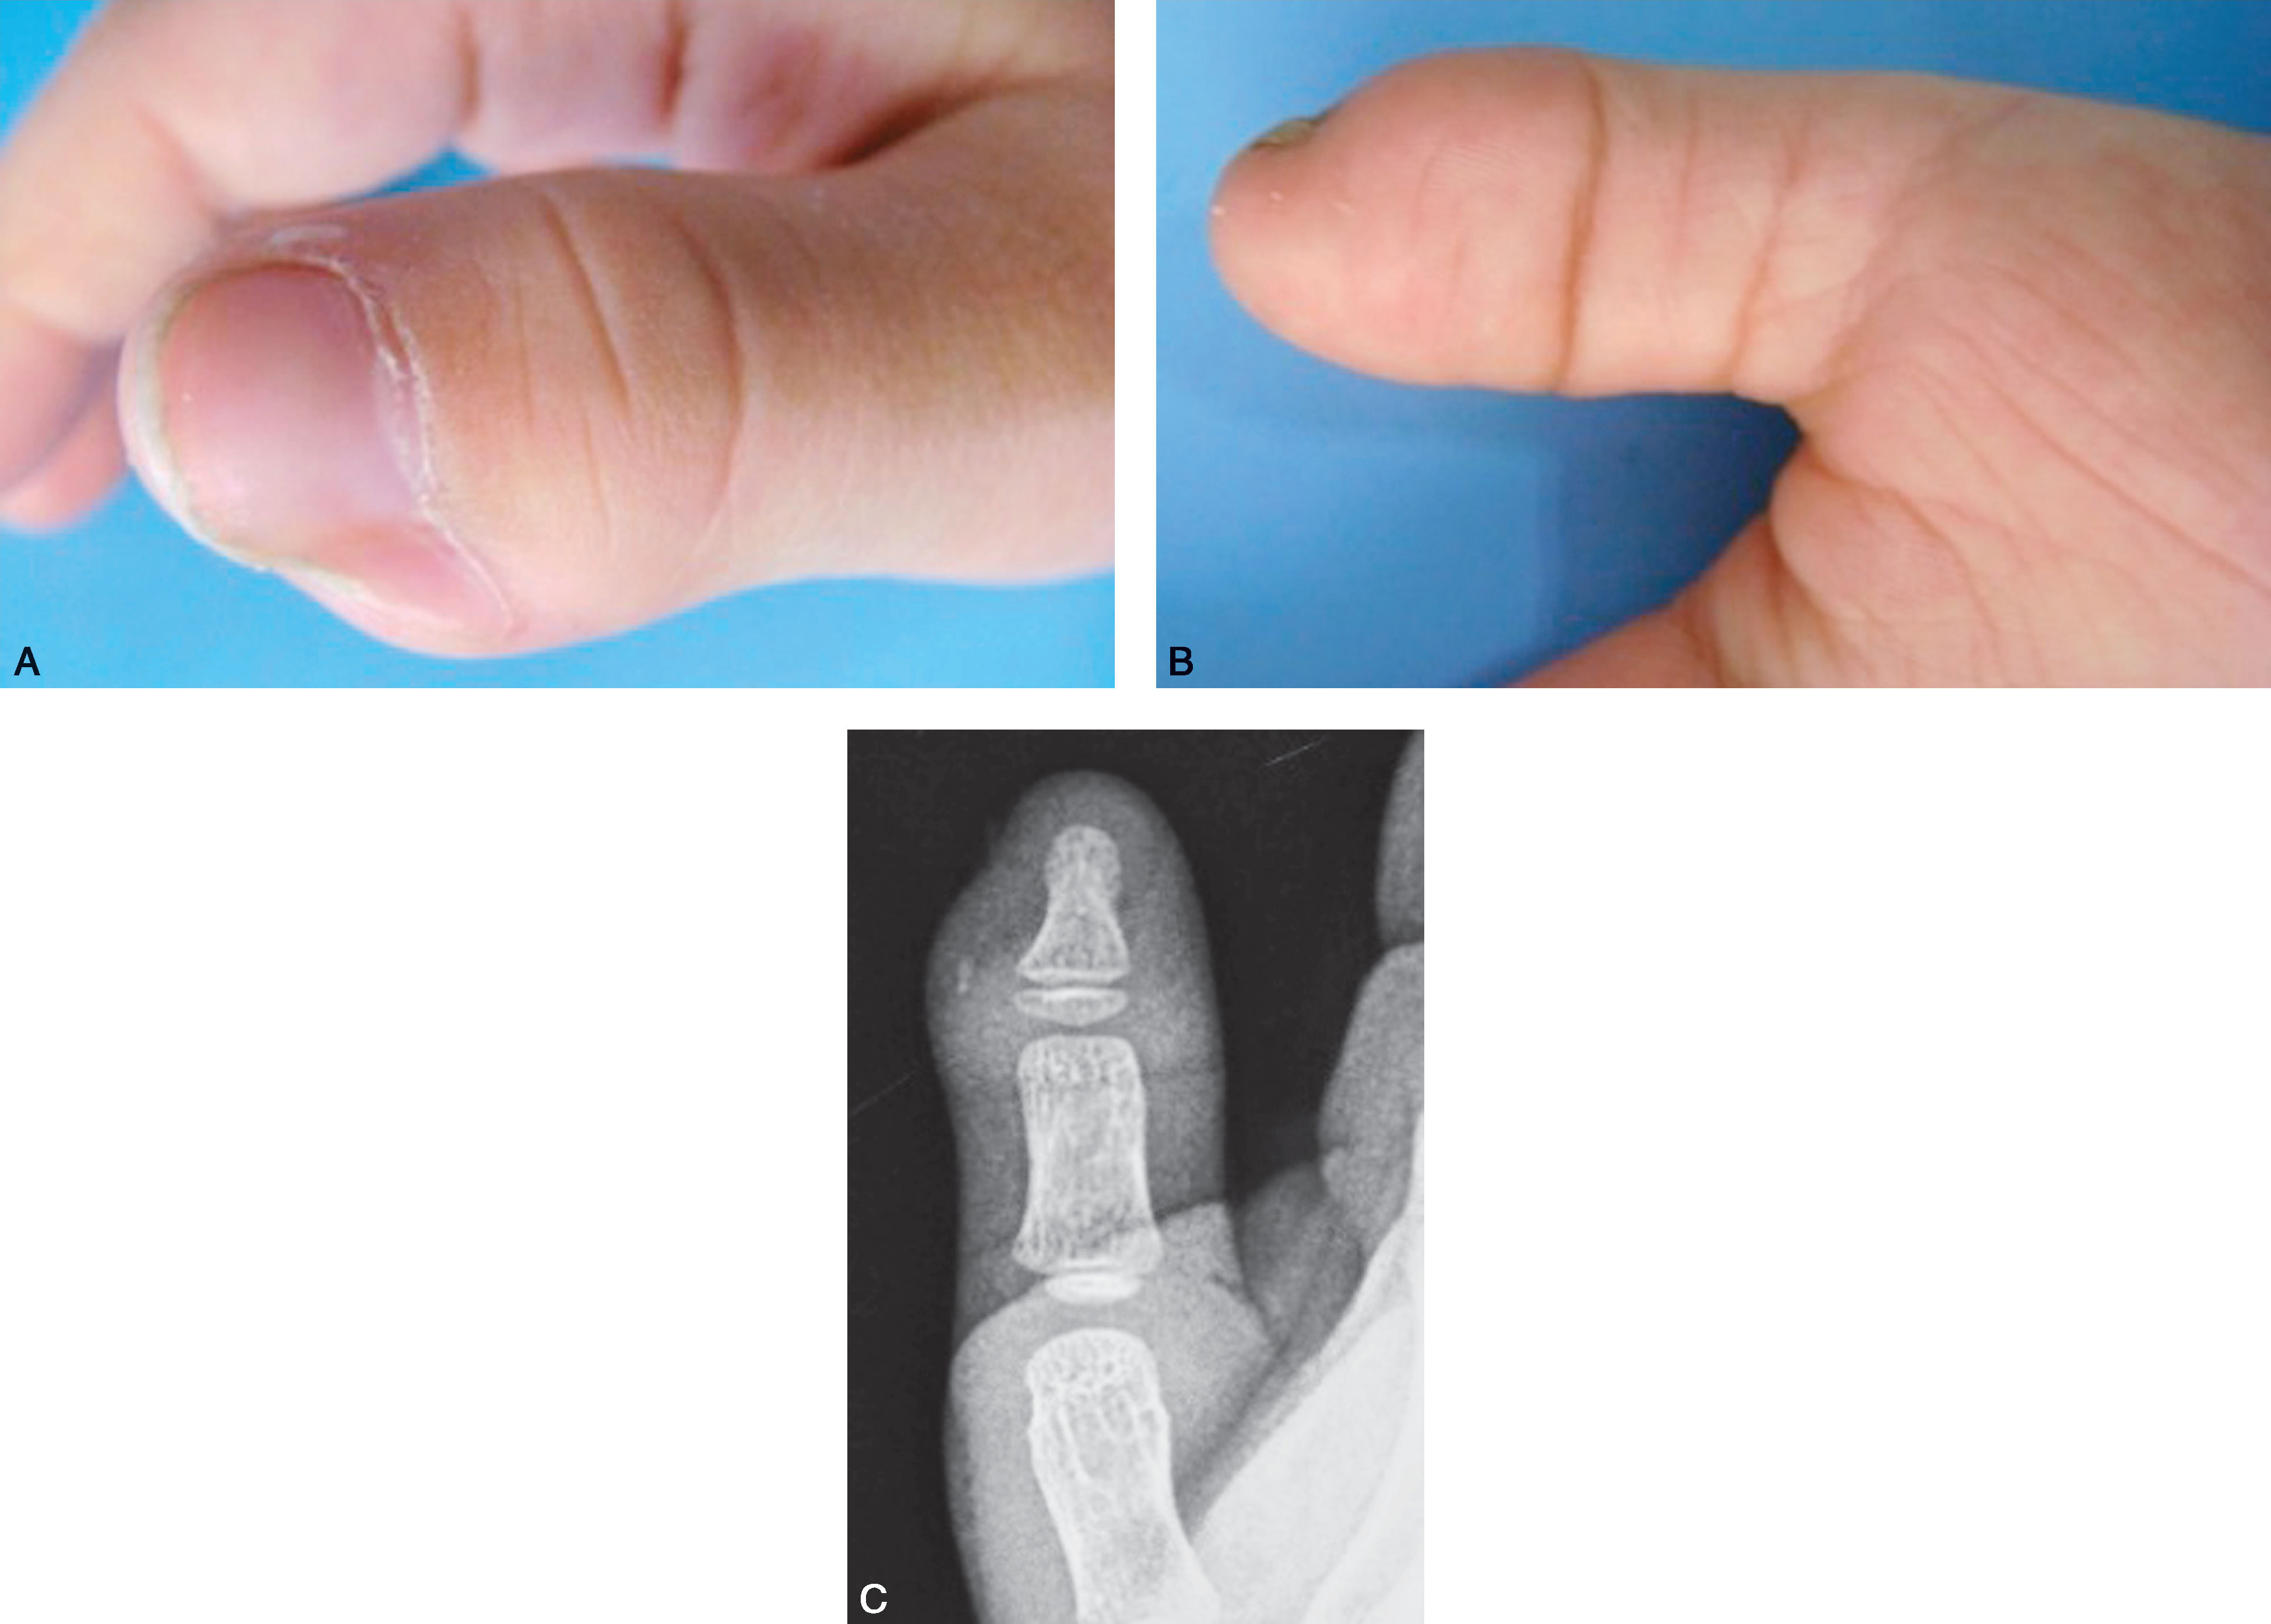

图2-1-3 Ⅰ型病例3

A.体位像显示主、次拇指指甲完全融合在一起,似一个指甲,应选择切除桡侧赘拇,然后需重建甲沟,并尽可能与对侧对称;B.X 线片显示,远节指骨分叉,桡侧部分细小,切除容易,但切除后应注意保持主拇指基底桡侧骨骺板开放。 由于远节指骨基底骨骺为不正常的倒V 形,术后骨骺生长仍可能异常,导致保留下来的远节指骨偏斜,需进一步截骨矫正

图2-1-4 Ⅰ型病例4

A.“镜影拇指”,主、次拇指外形及大小几乎一致;B.X 线片显示主、次拇指远节指骨几乎等大,是主、次拇指融合的适应证。 也可切除桡侧拇指,保留尺侧拇指,同时行保留的尺侧远节指骨基底骨骺端的桡侧闭合楔形截骨,但需保护骨骺板